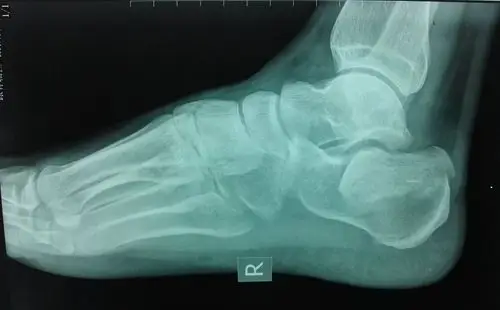

跟骨骨折病例